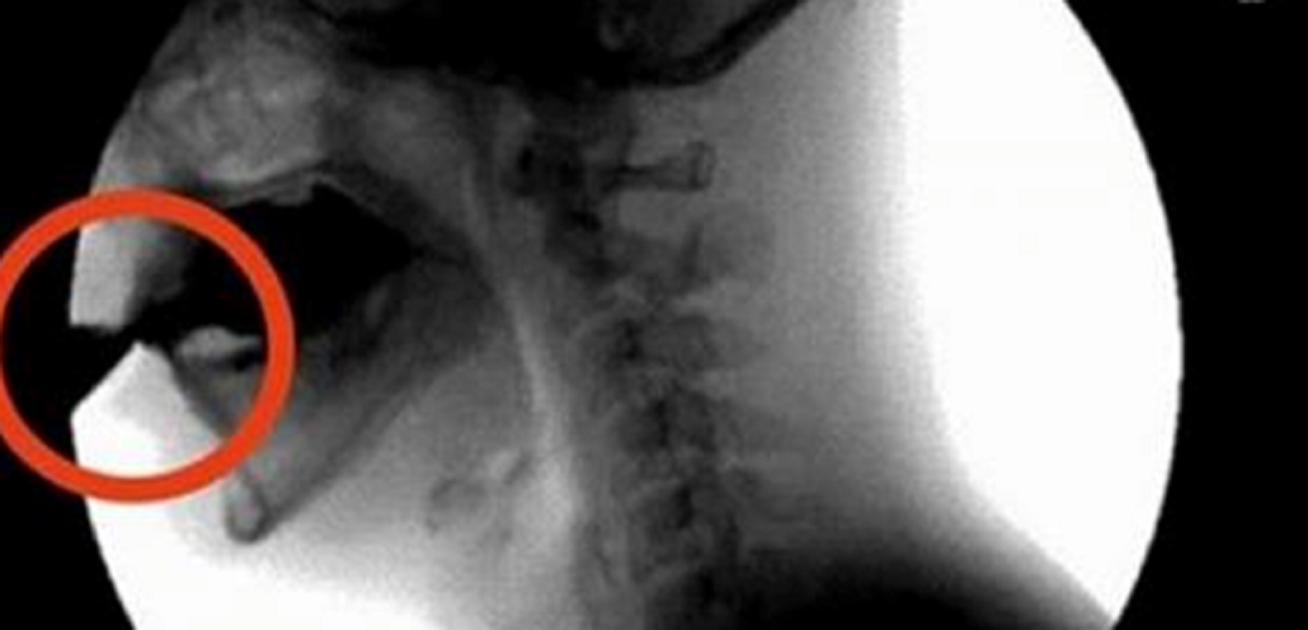

Po godzinie kwas fosforowy łączy się z wapnem, magnezem i cynkiem, więc metabolizm znowu przyspiesza, jest to jednak żmudny proces utrudniony olbrzymią dawką cukru i sztucznych barwników, które wypłukują nas z wapna.

Potem pojawia się efekt kofeiny, czyli pielgrzymki do toalety, a w związku z tym pozbywamy się z organizmu wapnia, magnezu, cynku, sodu, elektrolitów i wody.

Na sam koniec, gdy euforia minie, pojawia się stan podobny do hipoglikemii, tj. ilość glukozy we krwi drastycznie spada, przez co momentalnie czujemy się zmęczeni i poirytowani. Właśnie wypłukaliśmy z naszego organizmu budulec dla kości i jesteśmy na dobrej drodze do nabawienia się cukrzycy.